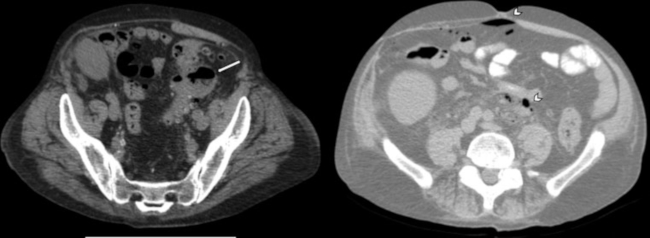

Estadio IB: Absceso < 4 cm (sin aire libre distante). Se recomienda internación hospitalaria con antibióticos EV y, en caso de fracaso terapéutico, drenaje percutáneo guiado por imágenes (ecografía o tomografía) (►Fig. 4).

Estadio IIA: Absceso > 4 cm (sin aire libre distante). Se recomienda drenaje percutáneo guiado por imágenes (►Figs. 5 y 6).